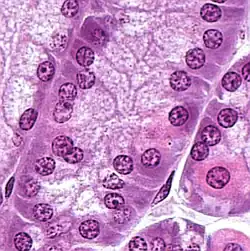

Las células principales gástricas, muestran un color violeta con la tinción H&E, debido a la gran proporción de retículo endoplasmático rugoso rico en ácido ribonucleico, basófilo por presentar afinidad característica por los colorantes básicos.

Se observa que estas células poseen grandes gránulos prominentes no teñidos con H&E de zimógeno en la región apical, y responsables de la secreción de enzimas proteolíticas en forma de proenzimas.[3]